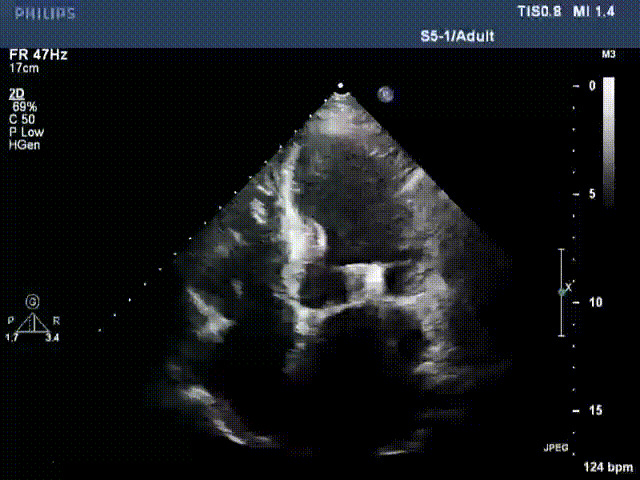

接受治療的是一例器質(zhì)性重度二尖瓣反流(DMR)患者,主訴“反復(fù)活動(dòng)后胸悶,氣促3年余”。術(shù)前超聲顯示,雙房增大,二尖瓣脫垂伴重度反流,輕度三尖瓣反流,輕度肺高壓,升主動(dòng)脈增寬。手術(shù)經(jīng)股靜脈-房間隔入路,采用全身麻醉插管,在TEE和DSA引導(dǎo)下完成房間隔穿刺。置入JensClip瓣膜夾系統(tǒng)后,在左房調(diào)整瓣膜夾的位置和軸向,后進(jìn)入左室,在TEE引導(dǎo)下捕捉二尖瓣前后瓣葉,并關(guān)閉瓣膜夾。經(jīng)TEE反復(fù)確認(rèn)手術(shù)效果后最終鎖定并釋放瓣膜夾。術(shù)后即刻超聲顯示瓣膜夾位置穩(wěn)定,功能良好,術(shù)前二尖瓣反流4+,術(shù)后0反流,肺靜脈逆流和左房壓都顯著好轉(zhuǎn),手術(shù)圓滿(mǎn)成功(以上數(shù)據(jù)都來(lái)源于醫(yī)院的臨床記錄)。術(shù)后患者狀態(tài)良好,目前已安排出院。

術(shù)前超聲提示二尖瓣重度反流